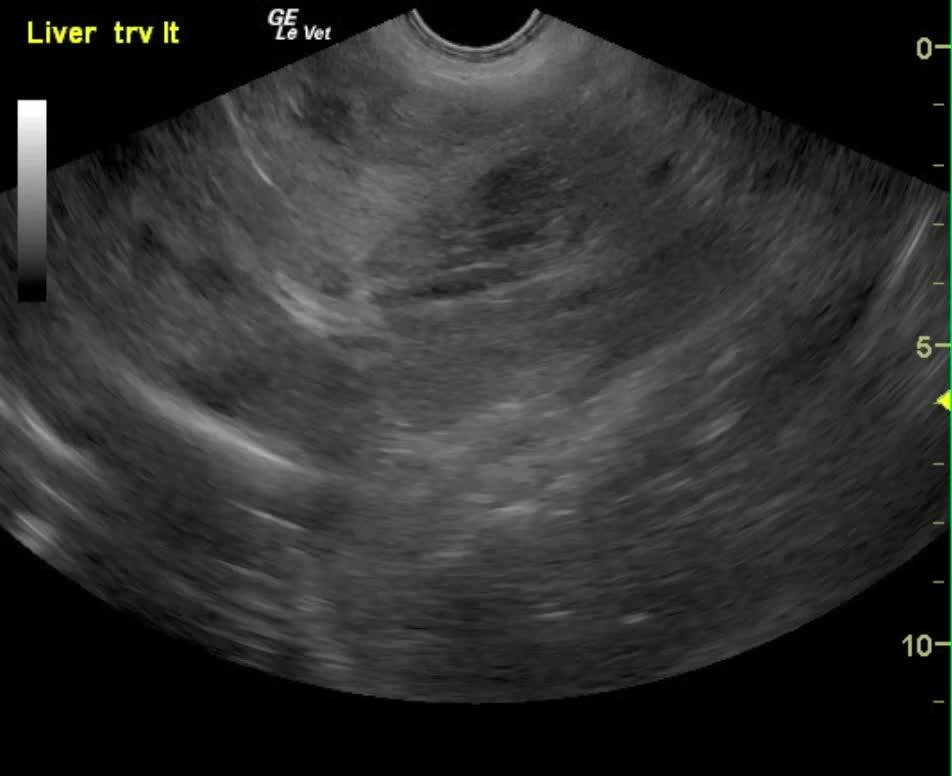

A 6-year-old FS shepherd mixed dog was presented for evaluation of vomiting, anorexia, loose stool, and polydipsia that had shown some response to Cerenia, Simplicef, and Denosyl therapy. Abnormalities on CBC and serum biochemistry were hemoconcentration, leukocytosis, and elevated ALT and elevated ALP activity.